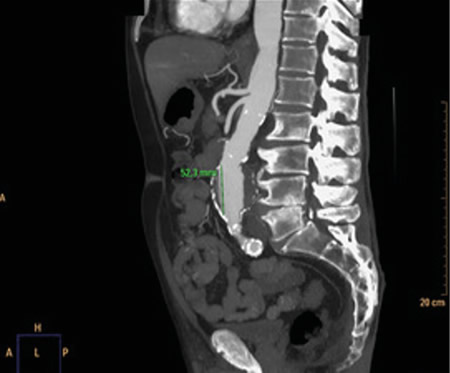

La rotura de aneurisma de aorta supone el síntoma principal en hasta un 25 % de los casos de la patología de aneurisma de aorta, que constituye una entidad potencialmente mortal. También puede aparecer con menor prevalencia como lumbalgia, coxalgia e, incluso, gonalgia, no comentándolo como dolor vertebral o neuropático, sino como irritación a nivel de psoas ilíaco como primera sintomatología.

Se estima que solo en un 50 % de los casos aparece la triada clásica del aneurisma, por lo que es necesario tener un alto nivel de alerta para sospecharlo, ya que la hipovolemia puede estar contenida por un hematoma peritoneal.

Figura 1